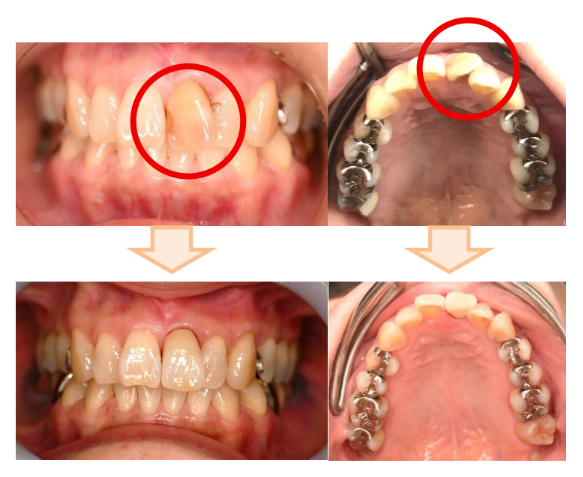

お口の中を拝見すると、左上の前歯に大きな詰め物があり、それが黄色く変色していました。また、ご自身の歯の部分も暗い茶色に変化しており、さらに歯が真っ直ぐではなく捻転(ねじれ)している状態でした。レントゲンで詳しく診察したところ、過去に神経を取り除いた歯であり、根の治療(根管治療)からやり直す必要があることがわかりました。

慎重に根の治療を行った後、仕上げの前の段階で、技工士の南部さんにも立ち会っていただきました。Yさん、院長、南部さん三者で「色、形、周りとのバランス」を細かく確認し、Yさんのご希望に沿うよう作り上げました。

治療後、鏡を見たYさんは、「自分の歯と見分けがつかないくらい自然です。曲がっていた歯を真っ直ぐ、きれいにしていただき、本当にありがとうございました!」と、大変喜んでくださいました。